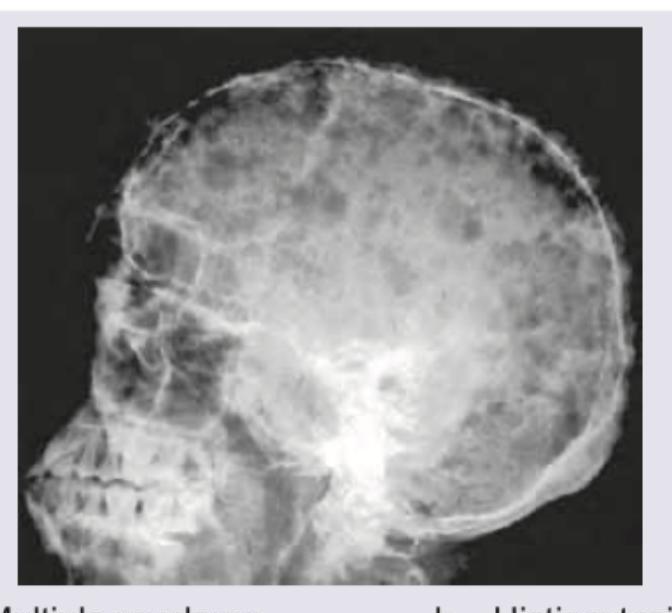

The findings in the following skull X-ray are most characteristic of:

Explanation: ***Multiple myeloma*** - The X-ray shows multiple well-defined, lytic, **punched-out lesions** throughout the skull, which is the classic presentation of multiple myeloma. - These lesions represent areas of bone destruction due to proliferation of **plasma cells** within the bone marrow. *Histiocytosis-X* - Histiocytosis X (Langerhans cell histiocytosis) can cause lytic skull lesions, but they are often described as **"beveled edge"** or **"hole within a hole"** appearance, which is not clearly depicted here. - While it can cause bony lesions, the widespread, uniformly punched-out appearance is more characteristic of multiple myeloma. *Hyperparathyroidism* - Hyperparathyroidism typically causes **generalized demineralization** of the skull, leading to a **"salt-and-pepper"** appearance, and possibly **subperiosteal bone resorption**. - It does not typically present with discrete, punched-out lytic lesions like those seen in the image. *Sickle cell anemia* - In sickle cell anemia, the skull X-ray may show **widening of the diploic spaces** and a **"hair-on-end"** or **"crew-cut"** appearance, especially in severe cases, due to marrow hyperplasia. - This is distinct from the multiple punched-out lesions observed in the provided image.